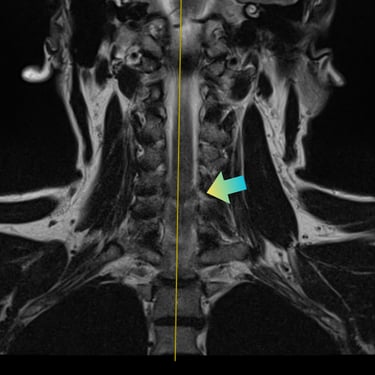

Hernia Cervical con Mielopatía: ACDF con Cage y Placa asistida con Monitoreo Neurofisiológico

La hernia cervical con mielopatía se produce por la compresión de la médula espinal, ocasionando dolor cervical, debilidad, alteraciones sensitivas y trastornos de la marcha. En casos de compromiso neurológico progresivo, la discectomía cervical anterior y fusión (ACDF) con cage y placa es una alternativa quirúrgica eficaz. La cirugía asistida con monitoreo neurofisiológico intraoperatorio permite evaluar en tiempo real la función neurológica, aumentando la seguridad del procedimiento. Este abordaje facilita una descompresión adecuada, estabilización del segmento cervical y favorece una recuperación neurológica segura y progresiva.